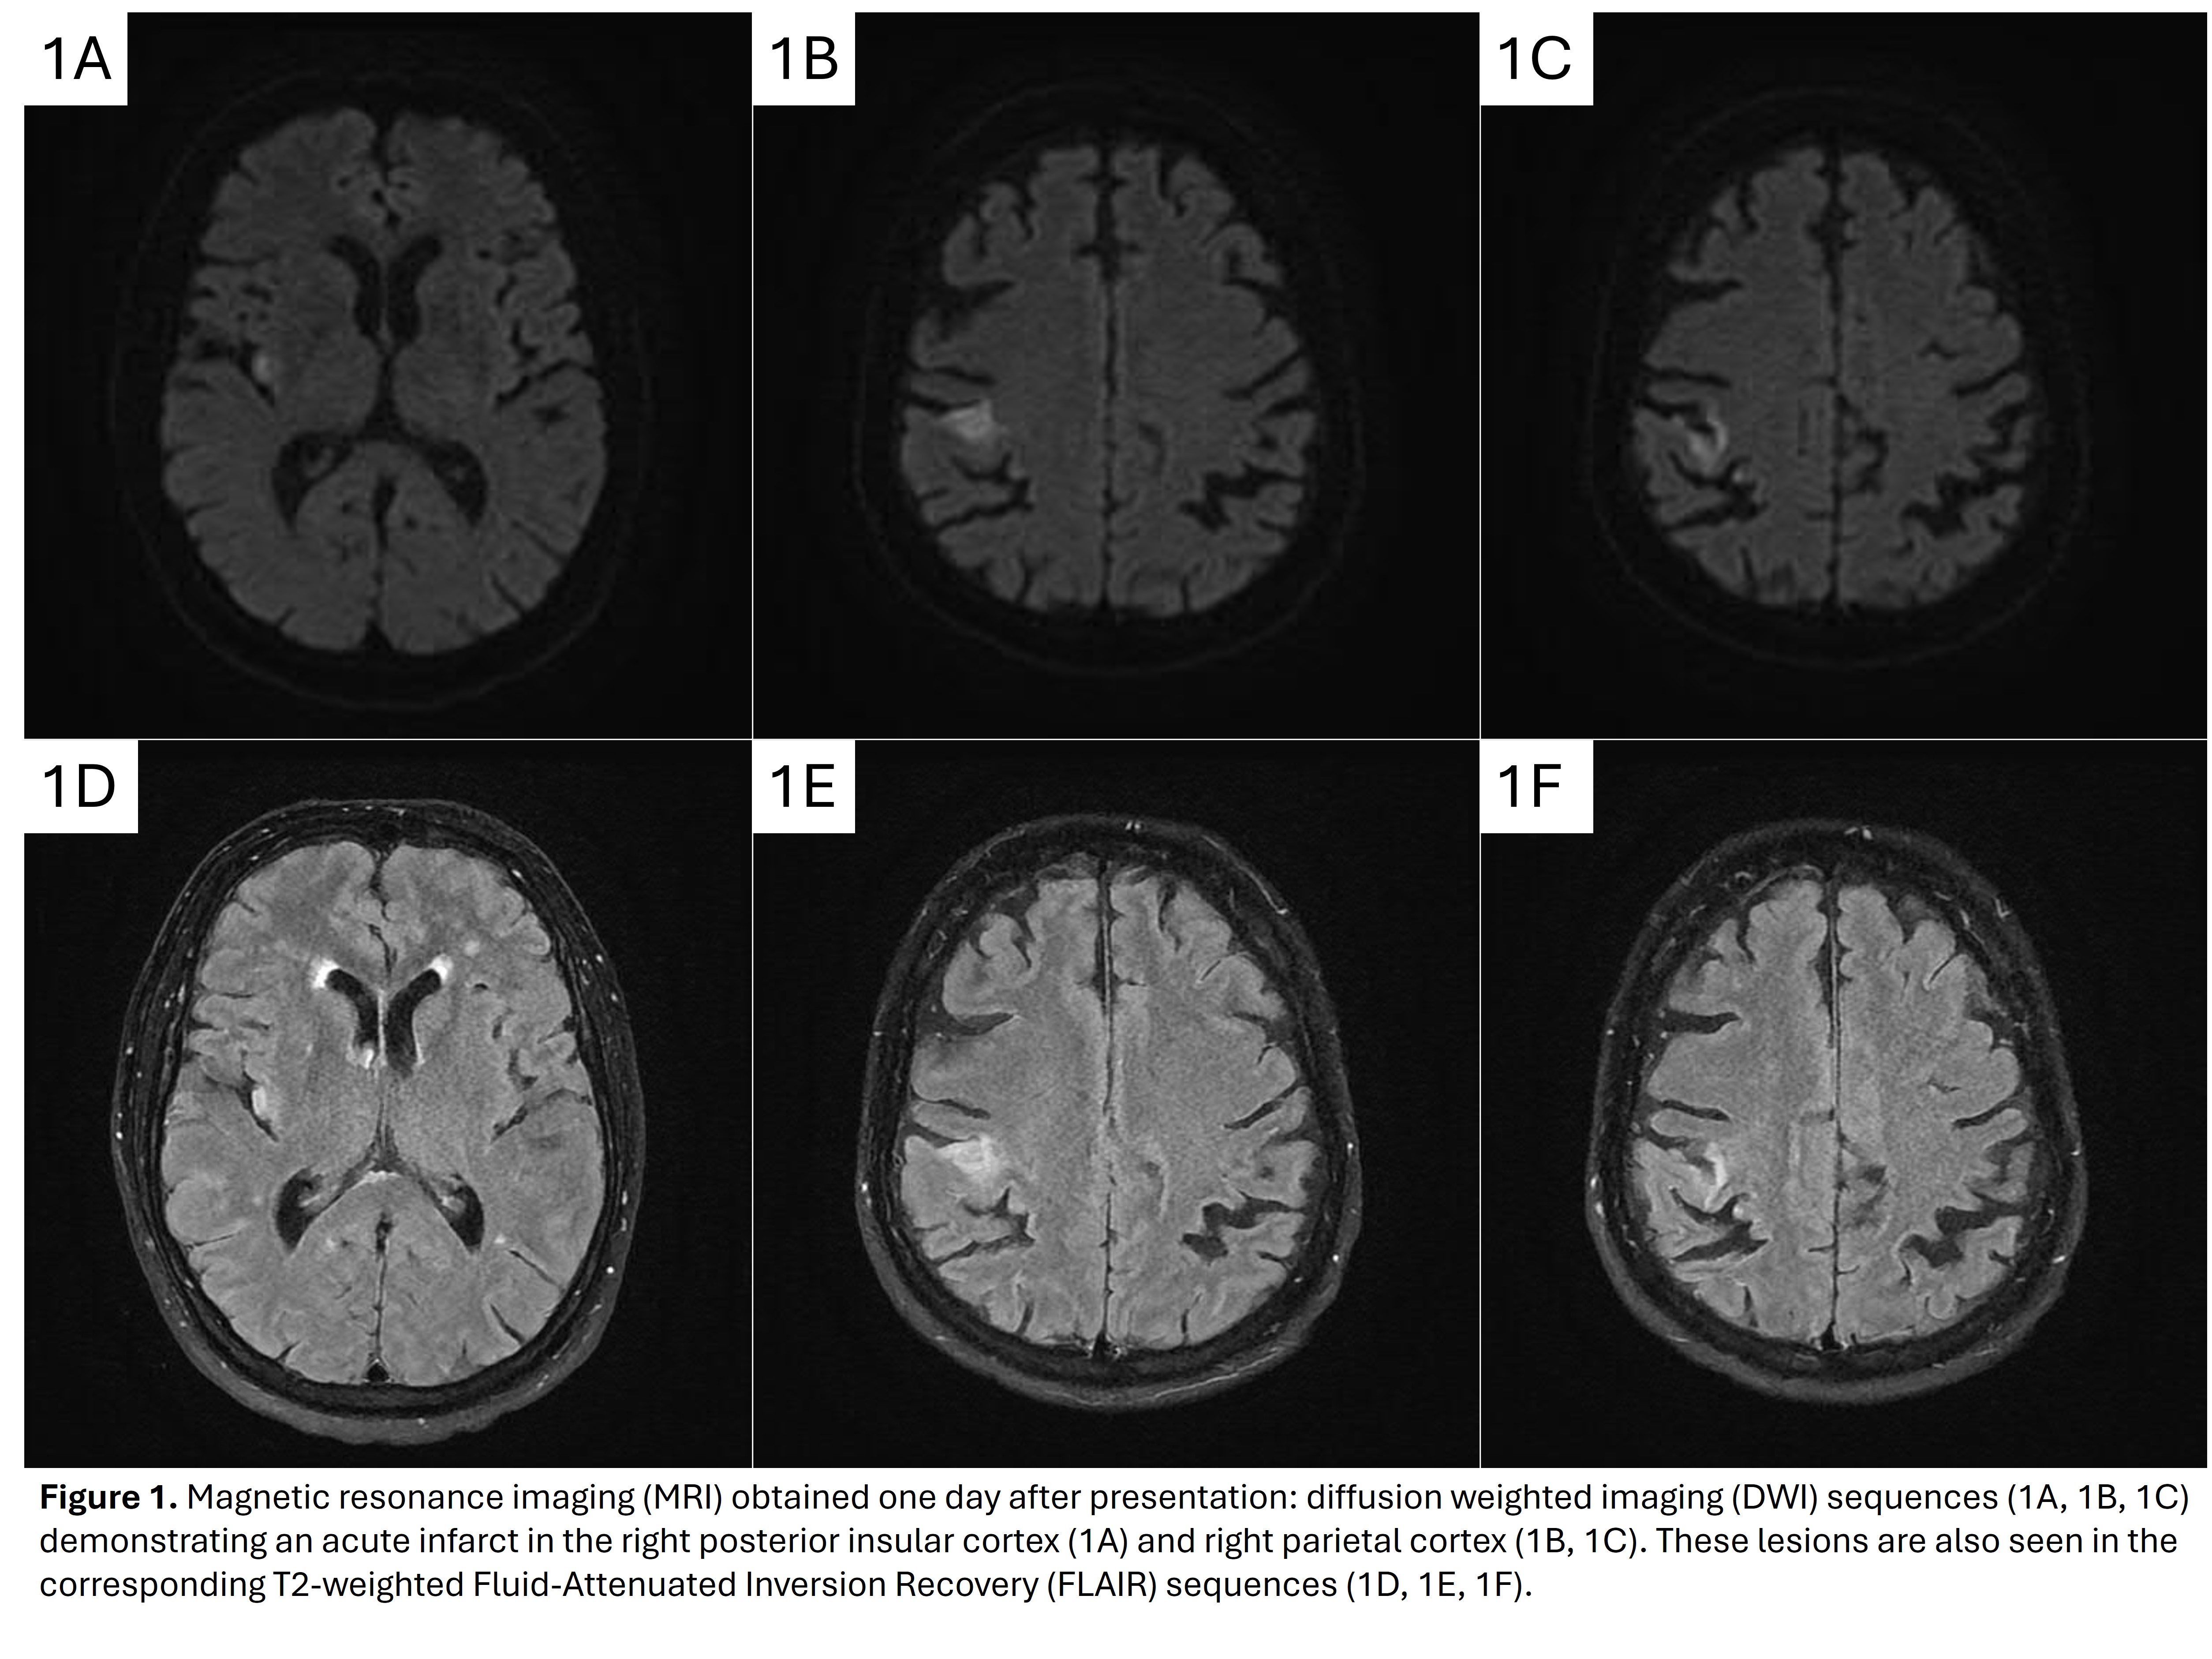

Method: A 69-year-old man presented with sudden left arm sensory loss, asomatagnosia, and weakness. CT-angiogram showed a right MCA-M2 occlusion. He received tenecteplase with rapid symptom improvement. Two hours post-thrombolysis, he exhibited involuntary, hyperkinetic, quasi-purposeful left arm movements seemingly incorporated into voluntary actions including grasping, lasting approximately 30 minutes. MRI revealed an acute infarct in the right posterior insular cortex and parietal lobe [figure 1]. Short-term EEG showed no epileptiform discharges.

Figure 1